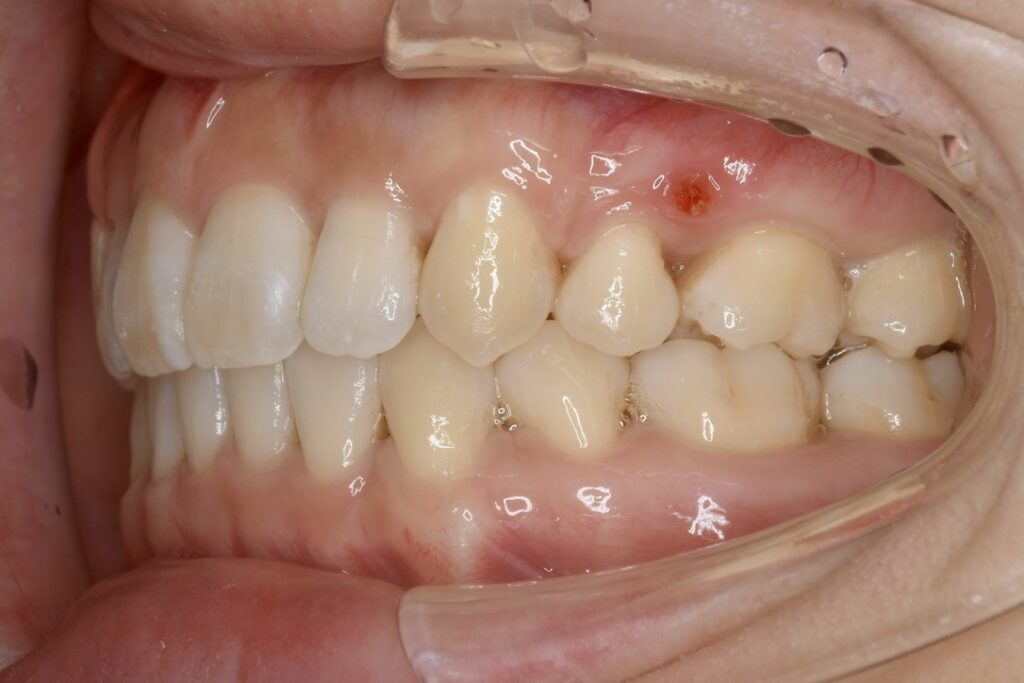

| 主訴 | 八重歯を治したい。 |

|---|---|

| 診断名・主な症状 | 上下前歯の叢生を伴う上顎前突 |

| 年齢 | 23歳 |

| 治療内容 | 上下とも歯を2本抜いて、前歯を後方に引きながら、でこぼこを治しました。 |

| 使用装置 | 表側矯正(ワイヤー) 矯正用ミニインプラント |

| 抜歯部位 | 上 両側4番目 下 両側5番目 |

| 治療期間 | 2年3ヶ月 |

| 通院回数 | 30回 |

| 費用 | 91万円程度(税別) 4255 |

| リスク・副作用 | 痛み、歯肉退縮、歯根吸収、抜歯に伴う出血や腫れが生じる可能性があります。 |